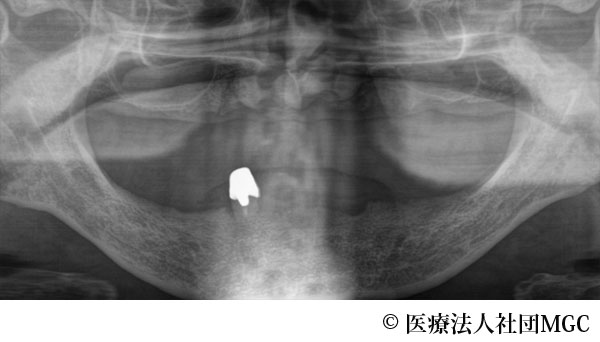

【症例2】上下All-on-4(オールオンフォー)

- 治療前

- 治療名

- 上下All-on-4(オールオンフォー)

- 費用

- 5,888,300円(税込)

- 期間

- 7ヵ月

患者様の症状

総入れ歯が合わず、噛めないとお困りでご来院されました。

治療法

ご相談の結果、患者様の生活の質(QOL)を向上させ、しっかり噛めるように上下All-on-4(オールオンフォー)を行いました。

治療結果

機能性、審美性ともに改善し、満足していただけました。

※治療結果は患者様によって個人差があります。

治療を行う上での注意点(リスク・副作用)

インプラント周囲炎の可能性、まれに歯が欠ける可能性があります。